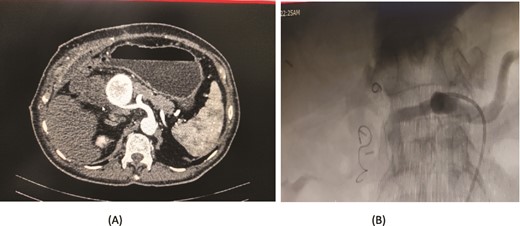

An 80-year-old male diagnosed with Mirizzi syndrome type 3 underwent a Roux-en-Y hepaticojejunostomy and cholecystectomy. His postoperative course was complicated by anastomotic site leakage on the 3rd postoperative day (POD). On the 14th POD, the patient presented with a sudden decrease in hemoglobin levels and per rectal (PR) bleeding. A CT angiogram revealed active bleeding from a branch of the jejunal artery, which was controlled through angioembolization. Two days after the first embolization, the patient developed intraperitoneal bleeding. A repeat CT angiogram showed active bleeding from the right hepatic artery, and a second angioembolization was performed to control the bleeding. Despite successful management of the bleeding episodes, the patient developed hospital-acquired pneumonia, which led to his deterioration. Unfortunately, the patient expired on the 30th POD (Fig. 6).

Case 6. (A) CT angiogram showing pseudoaneurysm and bleeding from right hepatic artery. (B) Embolization performed with coils.